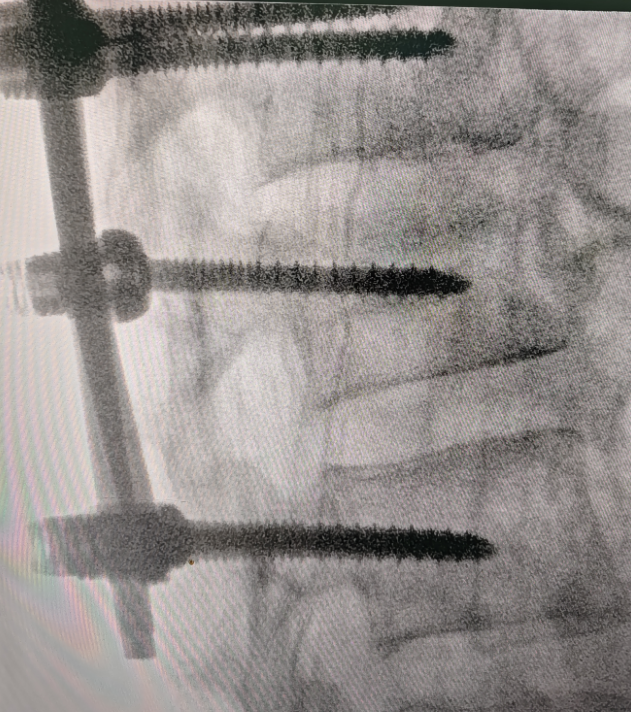

31歲的患者邊某因外傷致腰2椎體爆裂骨折前來(lái)就診,詹志強(qiáng)醫(yī)生帶領(lǐng)洛隆縣人民醫(yī)院醫(yī)生索東華爾丹、多吉次仁為患者行全麻下“后路腰2椎體骨折經(jīng)椎弓根釘棒復(fù)位內(nèi)固定術(shù)”。

手術(shù)耗時(shí)90分鐘,順利完成,術(shù)中5個(gè)釘?shù)狼锌陂L(zhǎng)度僅為2cm、出血僅約60ml,術(shù)中術(shù)后攝片見(jiàn)椎管內(nèi)占位的骨碎片已完全復(fù)位,椎體高度相比術(shù)前也得到明顯恢復(fù)。